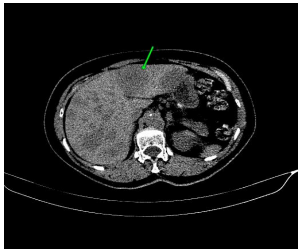

On palpation, there was an 8cm nodule in the right breast and mobile and fibroelastic axillary lymph nodes. There were no palpable nodules in the cervical or supraclavicular region bilaterally. A core needle biopsy was performed with an anatomopathological result of triple-negative grade 2 adenoid cystic carcinoma. Staging demonstrated two 1.1cm pulmonary nodules with soft tissue density suggesting metastasis. Abdominal tomography demonstrated liver nodules suggestive of secondary implants. The PET scan confirmed uptake in the lung and liver nodules, in addition to lytic lesions in S3. Liver biopsy confirmed implantation of adenoid cystic carcinoma. The patient was staged as T2N0M1. Chemotherapy was started with a regimen of Carboplatin, Paclitaxel and Pembrolizumab. After the third cycle of chemotherapy, the breast was reevaluated without showing any tumor reduction. The metastases also did not regress, and treatment was interrupted. The patient evaded the service until he returned in January 2024 complaining of pain in his right hip and difficulty walking. Chest and hip tomography showed an increase in lung lesions and the appearance of lytic metastasis in the iliac bone (figure 1, 2, 3).

Figure 2: